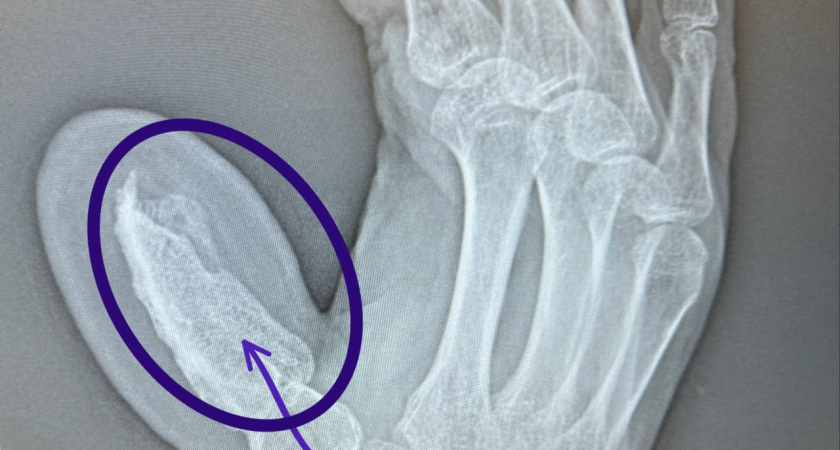

Ключевым этапом стала сложная операция, которую провели опытные хирурги Руслан Тельманович Радьков и Эльвира Рафиковна Кадырова. Они выполнили пересадку костного фрагмента длиной пять сантиметров материал взяли из гребня подвздошной кости, сохранив при этом питающую артерию. Для обеспечения необходимого кровоснабжения временно зафиксировали руку к животу пациента. Четырёхчасовая операция прошла без осложнений.

Полуторамесячный период после вмешательства был критически важен: врачи внимательно наблюдали за процессом приживления трансплантата. Как отмечают специалисты, подобная методика требует от пациента немалой выдержки не все готовы мириться с временными ограничениями. Однако именно такой подход обеспечил полноценное кровоснабжение пересаженной кости, что стало залогом успеха.

После того как трансплантат надёжно прижился, хирурги провели серию последующих вмешательств. Сначала отделили руку от живота и дождались заживления тканей. Затем выполнили операции по коррекции формы удалили избыточные участки кожи и подкожно‑жировой клетчатки, придав пальцу естественный вид.